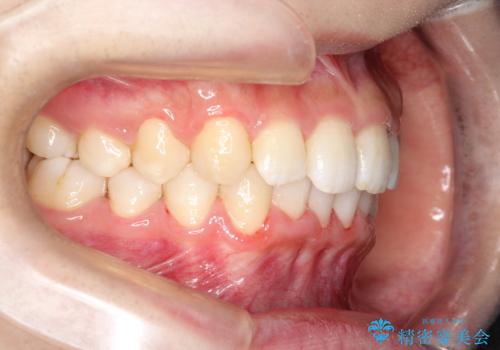

重度のガタガタのインビザラインによる非抜歯矯正

- 全体的なガタガタを気にされて来院されました。

抜歯矯正も考えられる状態でしたが、ご本人的になるべく歯を抜かない矯正を希望されました。

奥歯を後方に移動させるのと、歯と歯の間にわずかに隙間を作ることでスペースを確保して、抜歯をせず歯を並べる計画としました。

ガタガタの度合いが大きかったので少し時間がかかりましたが、非常に協力的な患者様でしたので、抜歯をせず計画通りに治療を終えることができました。